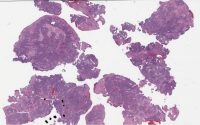

phs24-37622 1a control.svs

13944 x 23613

@ 40X